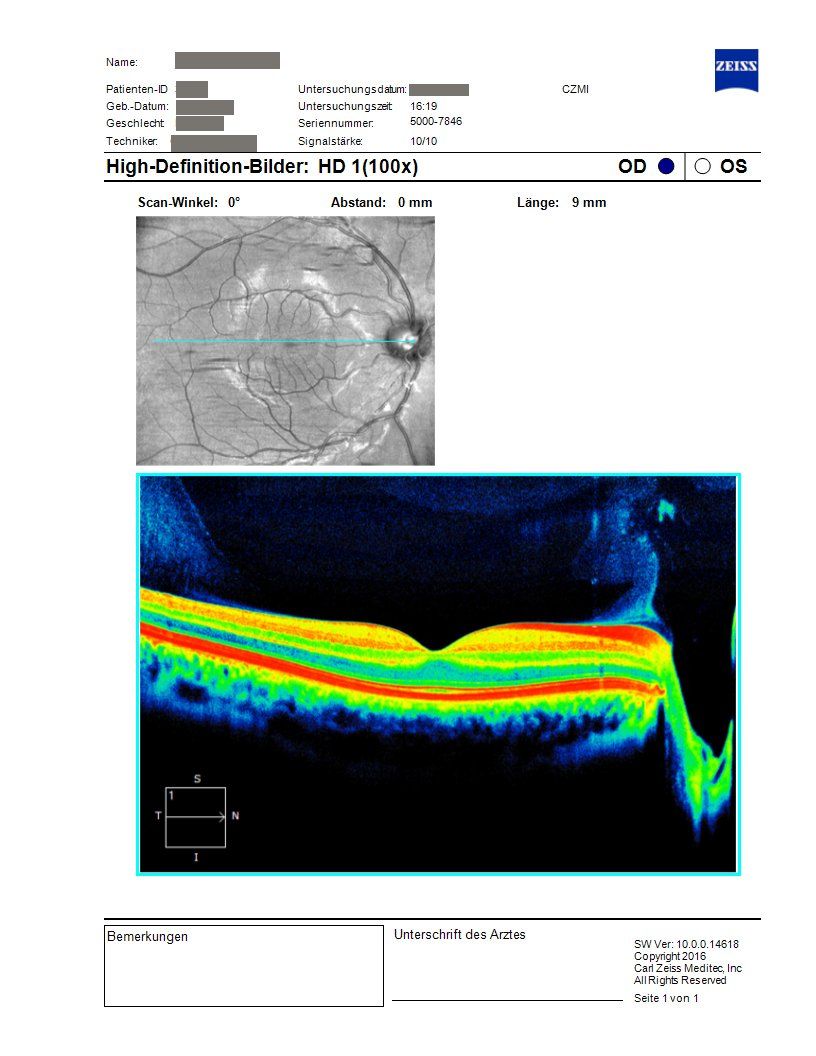

Die Optische Kohärenztomographie (OCT) ist ein modernes bildgebendes Verfahren, mit dem wir feinste Strukturen der Netzhaut, Makula und des Sehnervs hochauflösend darstellen können.

Die Untersuchung erfolgt völlig schmerzfrei und ohne direkten Kontakt zum Auge. Mithilfe von Lichtwellen entstehen präzise Querschnittsbilder, die Veränderungen sichtbar machen, noch bevor Beschwerden auftreten.

Besonders wichtig ist die OCT zur Früherkennung und Kontrolle bei Makuladegeneration, Glaukom oder diabetischen Netzhautveränderungen. Auch nach Operationen oder bei unklaren Sehstörungen liefert sie wertvolle Informationen. Auf diese Weise können wir Erkrankungen frühzeitig erkennen, den Verlauf eng überwachen und eine gezielte Behandlung einleiten, um Ihre Sehfähigkeit langfristig zu schützen.